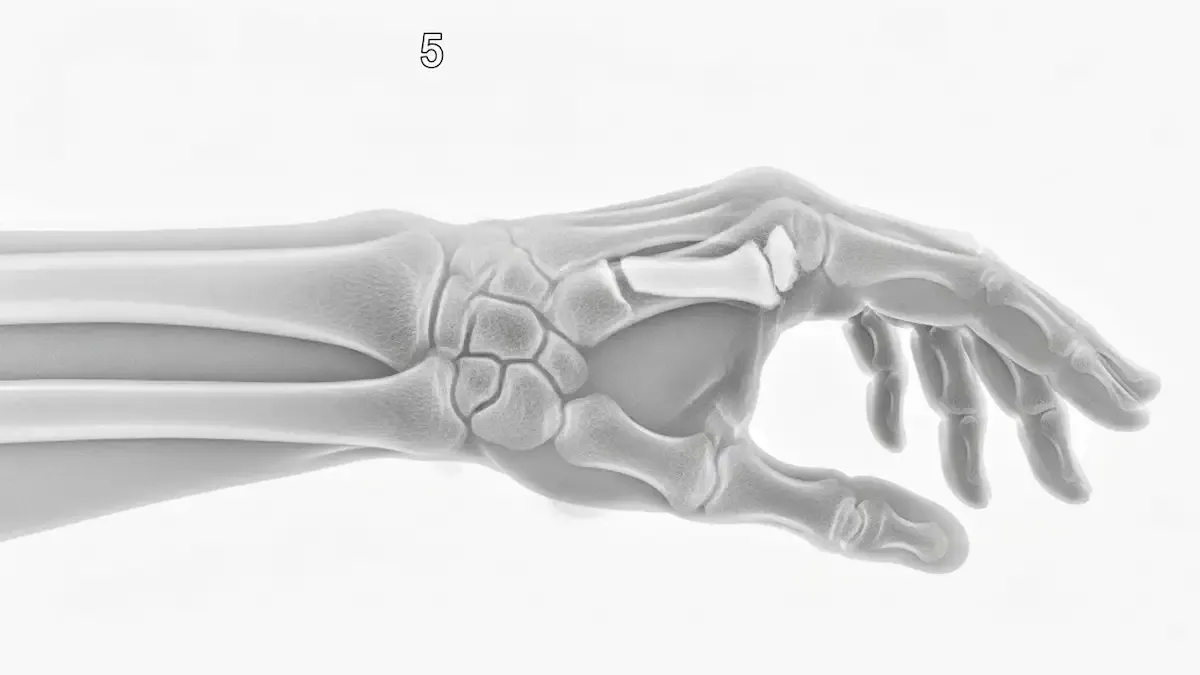

Como Saber Se Quebrei O Pulso? Sinais De Fratura

Após uma queda ou impacto direto na mão, surge uma dúvida comum no consultório: como saber se quebrei o pulso ou se foi apenas uma pancada? Essa diferenciação nem sempre é simples, já que fraturas, entorses e contusões podem causar sintomas...